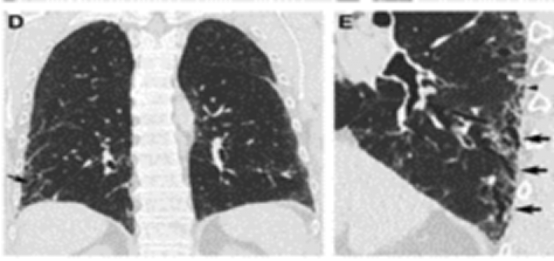

同时我们看到患者还伴有小叶中央型的磨玻璃样结节,可见吸气相(下图左)和呼气相(下图右)是有明显差别的。

ero为什么不显示叶俏教授:HRCT是发现和鉴别「过敏性肺炎」的重要环节,何种表现指向预后不良?使患者发病的危害因素躲在哪些环境中?_https://www.jmylbn.com_新闻资讯_第35张

病例:这位患者表现为马赛克灌注(Mosaic perfusion),与马赛克影的相同点是都出现在吸气相CT,而马赛克灌注是指的在正常密度的肺脏下,吸气相CT看到了一些低密度区,这些低密度区这提示血管或气道疾病,提示血管减少、气体陷闭。

ero为什么不显示叶俏教授:HRCT是发现和鉴别「过敏性肺炎」的重要环节,何种表现指向预后不良?使患者发病的危害因素躲在哪些环境中?_https://www.jmylbn.com_新闻资讯_第34张